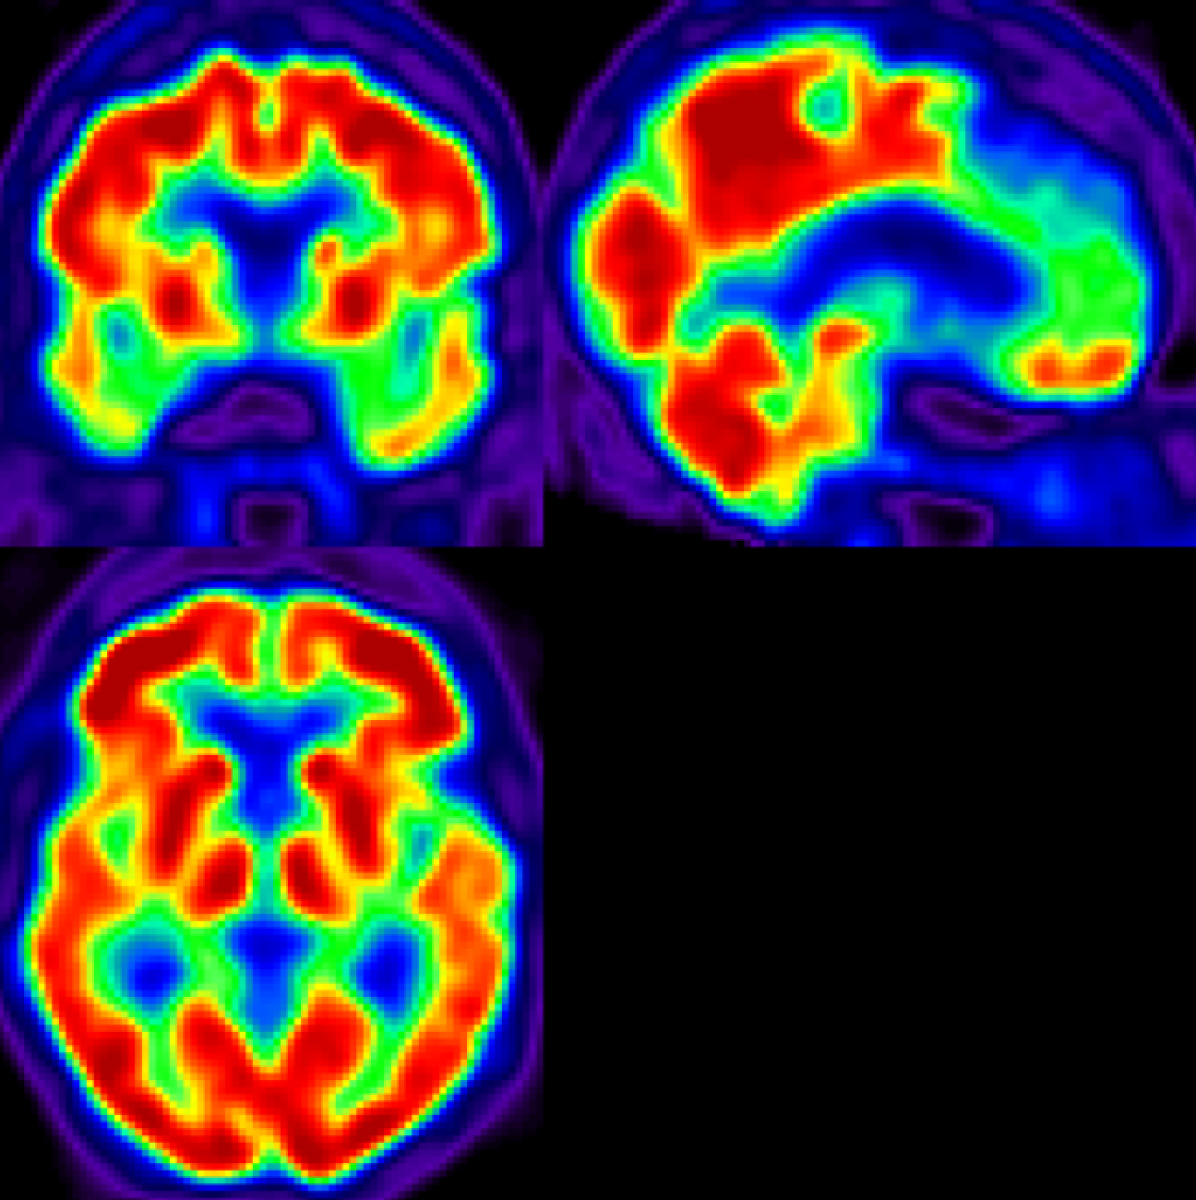

AD main effect is progressive neurological damage resulting from neuronal loss which occurs first in the hippocampus, temporal cortices, and parietal cortices [18, 19] (see Figure 1). As the disease evolves, neural damage progresses and affects the parahippocampal gyrus and amygdala [20]. In advanced stages, AD affects brain regions involved in primary bodily functions, complicating vital movements and becoming fatal to the patient [2]. Caused by the presence of neuritic plaques [21] and neurofibrillary tangles [22] in the affected neurons, this progressive neurological damage translates into neuropsychological and behavioural manifestations including worsened capacity to recall information, problems with planning and decision-making, generalized confusion, delusions, hallucinations, repetition of conversations, anxiety, among others [23, 2]. In addition, AD is typically accompanied by comorbidities such as major depressive disorders [24] which complicate the already poor situation of the patient, aggravating perceived health in a self-sustained downward spiral as proposed by recent life-course models [25] and contributing to severe reductions in life expectancy and other diffuse effects on health and well-being [26].

Figure 1: Regions of interest for research on early AD diagnosis in the human brain: hippocampus (red), temporal cortices (blue), and parietal cortices (green).